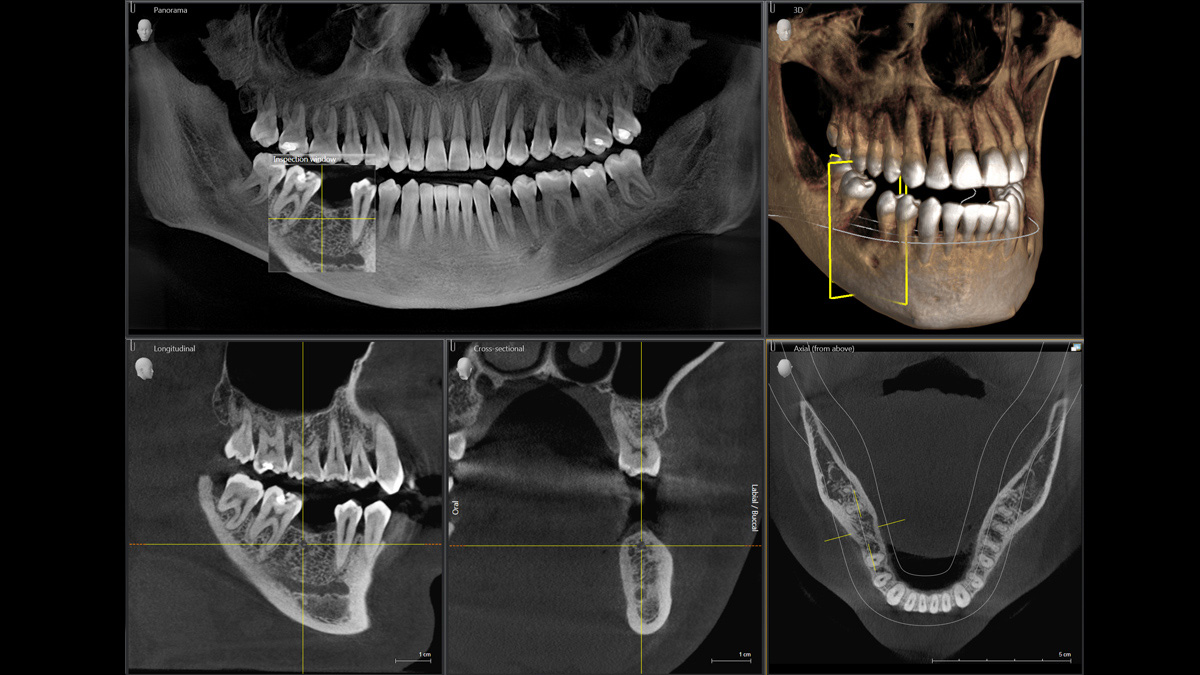

Mit dem Low Dose-Modus erhalten Sie 3D-Bilder im Dosisbereich einer 2D-Röntgenaufnahme. Im HD-Modus werden während eines einzelnen Umlaufs mehr als 800 Einzelbilder aufgenommen und zu einem 3D-Volumen mit bis zu 80 μm zusammengeführt. Der Vorteil für Sie: rauschärmere Aufnahmen in hoher Auflösung

Ø 5 cm x 5,5 cm bis Ø 8 cm x 8 cm (optional Ø 11 cm x 10 cm)

Nicht nur wegen meines Interesses an Technik finde ich die Kombination aus Direktumwandlung und rekonstruktivem Autofokus im Orthophos SL wirklich spannend. Die daraus resultierenden präzisen Bilder eignen sich hervorragend für die Interpretation. In Kombination mit der Volumenauswahl in 3D haben wir einen universell einsetzbaren Diagnostikpartner für unsere Praxis.“

Marcin Wojtunik, Facharzt für Mundchirurgie, Pfronten, Deutschland

Ein breites Spektrum an Volumengrößen für verschiedene diagnostische und klinische Anforderungen von Ø 5 × 5,5 cm bis Ø 11 × 10 cm